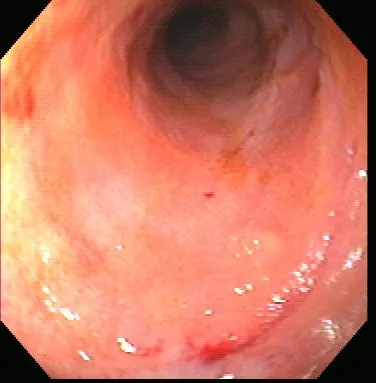

Gastroenteroscopy revealed a hard plastic foreign body (Figure 2) with curved, pointed ends. Points of the object were embedded in the gastric antral mucosa, resulting in hyperplasia. One of the curved points extended through the pylorus and hooked into the proximal duodenum (Figure 3). The endoscope could be passed around the foreign body into the duodenum, allowing biopsy of the duodenal mucosa. The gross appearance of the duodenal mucosa was normal (Figure 4). Attempts to remove the foreign body endoscopically were unsuccessful. Before the dog was sent to surgery for removal of the foreign body, colonoscopy was performed. The colon appeared normal on gross inspection (Figure 5). Biopsies were obtained from the cecum; ascending colon; transverse colon; and proximal, middle, and distal descending colon. At surgery, a gastrotomy incision was made in the pyloric antrum and the foreign body was forcefully removed. It was a plastic object used to secure the legs of a turkey carcass.

Healthy proximal duodenum